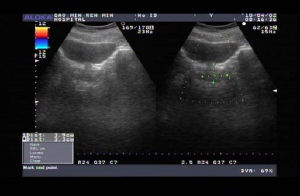

1、常規、生化檢查:了解尿液、腎功能情況及一般情況。酚紅(PSP)排泄試驗能較早提示腎盂積水及腎功能情況。2、殘餘尿量測定:多用B超測定(常用公式:殘餘尿量=上下徑×前後徑×0.5,殘餘尿量少時可用上下徑×左右徑×0.7),導尿法測定殘餘尿更精確。